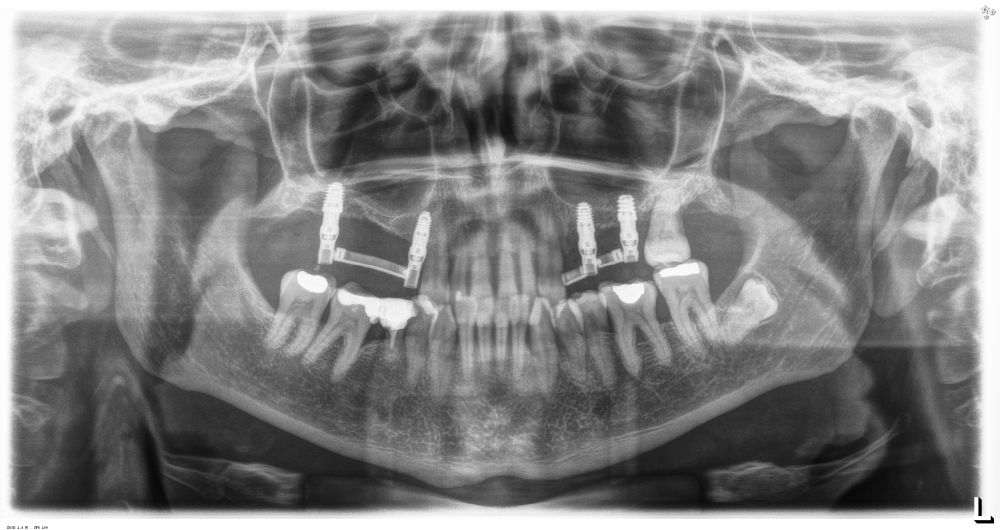

Una vez colocados los implantes, podemos realizar incluso carga inmediata, ya que, aun en condiciones de baja densidad y escasa altura ósea residual, con el protocolo anteriormente descrito se logra la estabilidad primaria suficiente (Figuras 25 y 26). Elaboramos una prótesis de carga inmediata atornillada sobre transepitelial (colocados en el momento de la cirugía y mantenidos posteriormente para no romper el hermetismo), confeccionada en resina con una estructura de barras articuladas. Esta prótesis nos proporciona carga progresiva mientras se produce la integración de los implantes, lo que favorece este proceso y permite reconstruir el patrón oclusal perdido, dado que presenta múltiples ausencias dentales del sector posterior maxilar. La carga progresiva en los implantes dentales es una técnica que permite una transición gradual de fuerzas sobre el implante, favoreciendo la adaptación biológica y la estabilidad ósea a lo largo del tiempo. En lugar de aplicar una carga inmediata completa, se introduce una presión controlada y creciente durante el periodo de cicatrización, lo que facilita una mejor osteointegración y reduce el riesgo de sobrecarga temprana. Este enfoque es especialmente útil en casos donde la calidad ósea es comprometida o cuando se busca una mayor predictibilidad en el tratamiento12.

Transcurridos 6 meses desde la carga inicial progresiva, se puede elaborar la prótesis definitiva, trasladando los parámetros de la prótesis provisional (Figura 27). La paciente continúa en seguimiento durante un año, realizándose radiografías de control para el monitoreo del hueso crestal, sin encontrarse pérdida ósea asociada en ninguno de los implantes (Figuras 28-29).